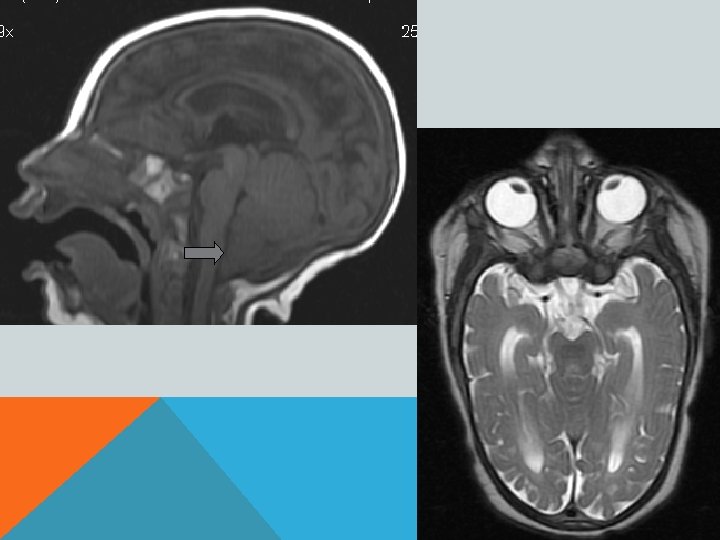

Диагноз подтверждает прежде всего МРТ. Дифференциальная диагностика • Опухоли спинного мозга обычно проявляются более локальной и быстро нарастающей симптоматикой • Травма спинного мозга • При боковом амиотрофическом склерозе двигательные расстройства никогда не сопровождаются выпадением чувствительности

ПОРОК АРНОЛЬДА-КИАРИ 1 Увеличение миндалин мозжечка, их опущение в большое затылочное отверстие и далее, в спинномозговой канал- «нижний» вариант. Характерно образование сирингомиелической полости в шейном отделе спинного мозга. Основные клинические проявления- сирингомиелия.

ПОРОК АРНОЛЬДА-КИАРИ 2 Увеличение миндалин мозжечка, их опущение в большое затылочное отверстие и далее, в спинномозговой канал. «Щелевидный» 4 -й желудочек. Гипоплазия подушки моста мозга. Гипо-/аплазия мозолистого тела. Сирингомиелическая полость в шейном отделе спинного мозга. Фенестрация фалькса (серпа мозга) и т. д. В 70% сочетается со спинномозговой грыжей.